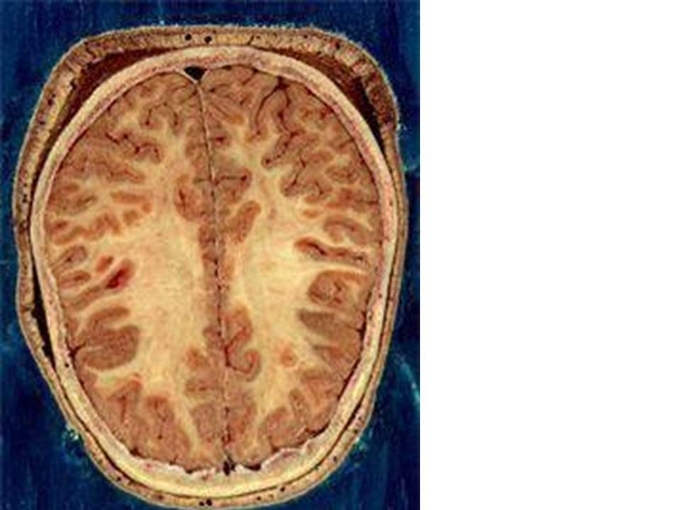

과체중, 비만 아이는 또 뇌의 표면을 구성하는 피질인 회색질(gray matter)의 가장 바깥층 두께가 얇은 것으로 나타났다. 이는 뇌의 집행기능(executive function)이 손상됐다는 의미다.

뇌는 신경 세포체로 구성된 겉 부분인 대뇌 피질과 신경 세포들을 서로 연결하는 신경 섬유망이 깔린 속 부분인 수질로 이루어져 있다. 피질은 회색을 띠고 있어 회색질, 수질은 하얀색을 띠고 있어 백질이라고 불린다.